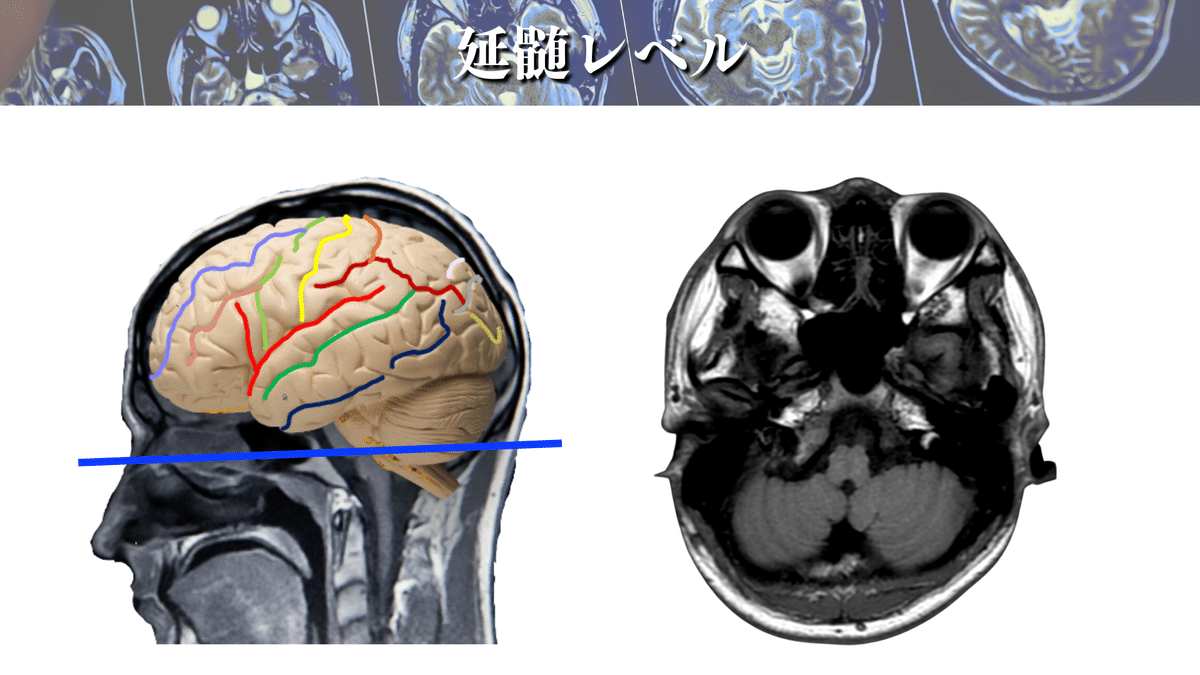

延髄レベル

詳しい場所も見ていきましょう!

CSTはよく「錐体路」と言われていますが、これはこの延髄錐体を通過するからになります👍

この錐体を通過する際に対側に交叉するので、脳とは反対側の四肢の運動を制御しているわけですね‼️

補足:LCSTとACST

CSTは延髄錐体で80〜90%が交叉して脊髄の側索を通ります。これをLCSTと言います🖐️

残りの線維は非交叉性で前皮質脊髄路(ACST)と言いまして、脊髄の前索を下降していきます🏃♀️

ACSTの主な特徴は以下になります⬇️

・胸髄レベルでほぼ消失

・脊髄レベルでは一部が前白交連で交叉する

・普段はマスキングされていることが多い

・ヒトでは個体差に富み、体幹の制御に関わることもある

DTTで確認してみても、前方の延髄錐体を通過していることが分かりますね👍

ちなみに、延髄錐体で交叉をするわけですが、錐体交叉後に損傷された場合には損傷側と同側の運動麻痺が出現しますので、損傷レベルには注意してくださいね🙇♂️